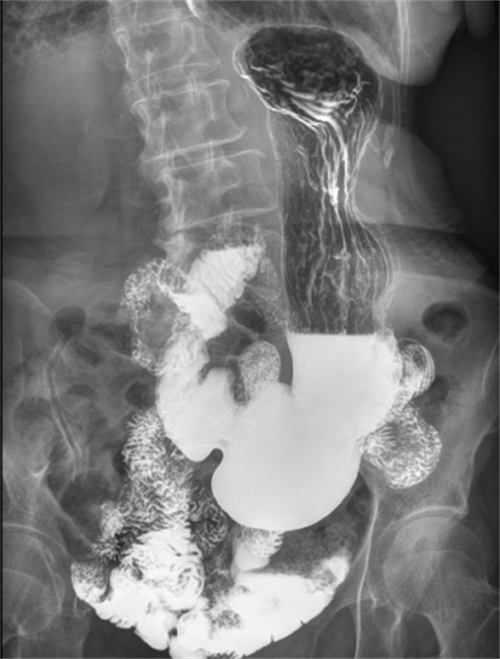

从功能方面上,动态DR是一款多功能DR,可以进行数字化x线摄影、数字化x线造影、数字化x线透视等,相较于静态DR,动态DR具备更多的临床应用场景。;从技术方面:动态DR是使用多功能动态数字探测器成像的直接数字化X射线摄影系统;从临床方面:动态DR具有(17inch×17inch)高清拍片、大幅面(17inch×17inch)透视、毫秒级高清点片、可视化造影、全身拼接、视频实时保存回放等支持精准诊断的功能。(第一张图为动态DR诊断隐匿性病灶临床图像,第二张图像为上消化道造影图像)